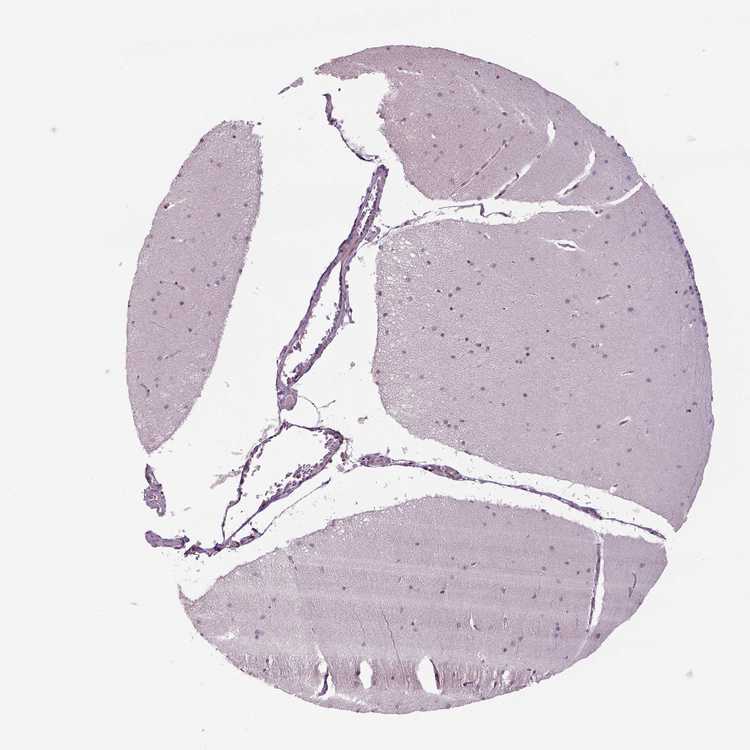

BRAIN CEREBELLUM Show tissue menu

CEREBELLUM - Expression summary

Protein expression

Cerebellumi

On the top, protein expression in current human tissue, based on all annotated cell types, is reported with the units not detected (n), low (l), medium (m) and high (h). Underneath, protein expression in each annotated cell type are reported using the same units.

Protein expression data is based on knowledge-based annotation. For genes where more than one antibody has been used, a collective score is set.

If knowledge-based annotation could not be performed for a gene, no data is displayed here. View antibody staining data further down this page.

h

m

l

n

Cells in granular layer: Not detected

Cells in molecular layer: Not detected

Purkinje cells: Not detected

CEREBELLUM - Antibody stainingi

Antibody staining in the annotated cell types in the current human tissue is reported as not detected, low, medium, or high, based on conventional immunohistochemistry profiling in selected tissues. This score is based on the combination of the staining intensity and fraction of stained cells.

Each image is clickable and will lead to virtual microscopy that enables deeper exploration of all samples and also displays staining intensity scores, fraction scores and subcellular localization as well as patient and tissue information for each sample.

Antibody HPA069497Antibody CAB002786Antibody CAB069881

Purkinje cells Not detectedNot detectedNot detected

Cells in granular layer Not detectedLowNot detected

Cells in molecular layer Not detectedNot detectedNot detected